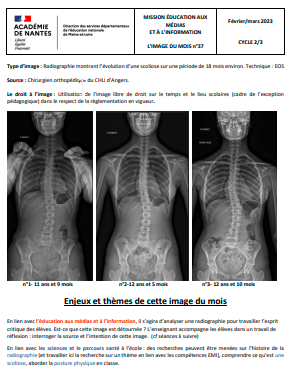

N°37

Février-mars 2023

Cycle(s) : C2-C3